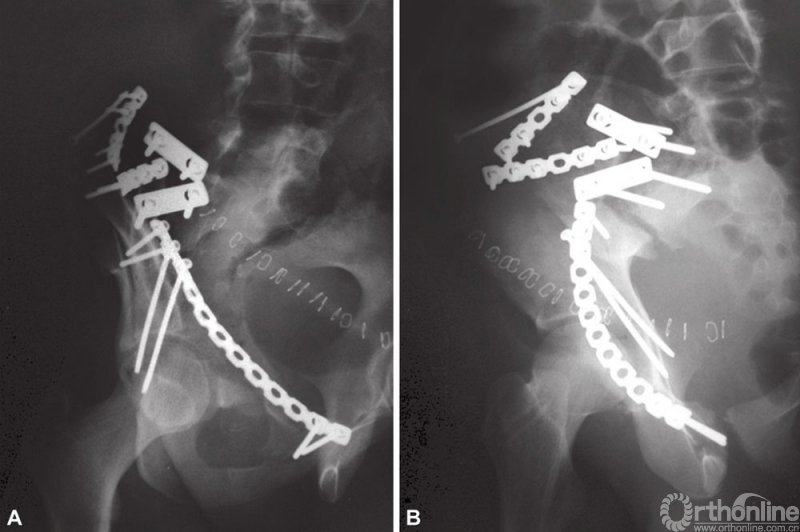

A和B从后向前进行复位,放置骶髂关节钢板进行固定,通过前入路放置长的后柱螺钉

如果骨折非常粉碎,需要从后向前进行固定。前柱骨折块外旋是常见的畸形。因此,在髂嵴上置入Shanz针,施加内旋的力量,纠正骨块外旋畸形。可以在直视下使用复位钳复位髂骨翼骨折块和累及髂嵴的骨折块,也可以使用Shanz针纠正骨折旋转和移位。在骨盆边缘,采用12、14或者16孔预弯的骨盆重建钢板进行确定性固定。

A和B(A)前方入路固定横行骨折;(B)骨盆内钢丝环扎

32岁男性患者,高处坠落伤后左侧髋臼出现横行骨折。采用髂腹股沟入路处理骨折。采用骨盆内钢丝环扎辅助复位和固定骨折。